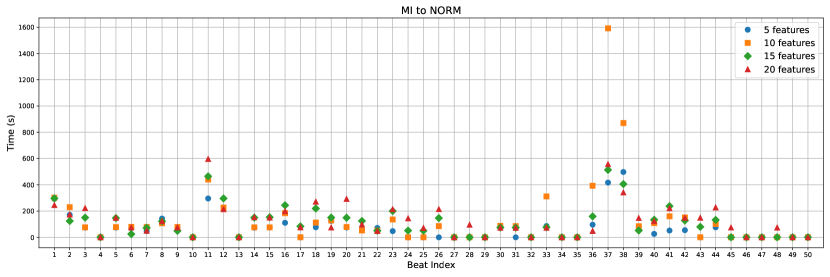

Through our experimental investigations, we discovered that utilizing 19 features is sufficient for extracting counterfactual instances. A lesser number of features is preferable for counterfactuals as it yields better and more reasonable explanations. To conduct a comprehensive assessment of counterfactuals, we generated distinct scenarios involving sets of 5, 10, 15, and 20 features. This evaluation encompassed considerations such as the time taken for generation (refer to Appendix Figure C.6 and C.7) and a comparative analysis of the most influential features affecting the outcomes. The F1 scores for each feature set are as follows: 81.40% for 5 features, 83.50% for 10 features, 85.83% for 15 features, 86.59% for 20 features, and 88.47% for 97 features.

The generation time exhibits variations based on the feature count. When altering from NORM to MI (Appendix Figure C.6), the generation times are as follows: for the case of 5 features, it takes 17.71 ± 33.0 seconds; for 10 features, it takes 35.35 ± 45.62 seconds; for 15 features, it takes 46.86 ± 53.35 seconds; and for 20 features, it takes 58.06 ± 61.8 seconds. Notably, there is a consistent escalation in both the average and standard deviation of generation times with an increase in the feature count.

However, when considering the change from MI to NORM (Appendix Figure C.7), the generation times exhibit different behavior: for 5 features, it takes 73.2 ± 106.46 seconds; for 10 features, it takes 132.64 ± 259.36 seconds; for 15 features, it takes 111.94 ± 121.75 seconds; and for 20 features, it takes 127.48 ± 129.02 seconds. In this case, the observed pattern in generation time does not follow the same trend as seen in the previous scenario. Table 2 demonstrates that the MI to NORM transition poses greater challenges for the model. This is evident from the observed increase in overall counterfactual generation times, which can be attributed to this particular transition being more demanding in optimization process.

To make the durations more conspicuous, you can see the elapsed times for sample 50 beats with 5, 10, 15, 20 feature counts in Figure C.6 and C.7.